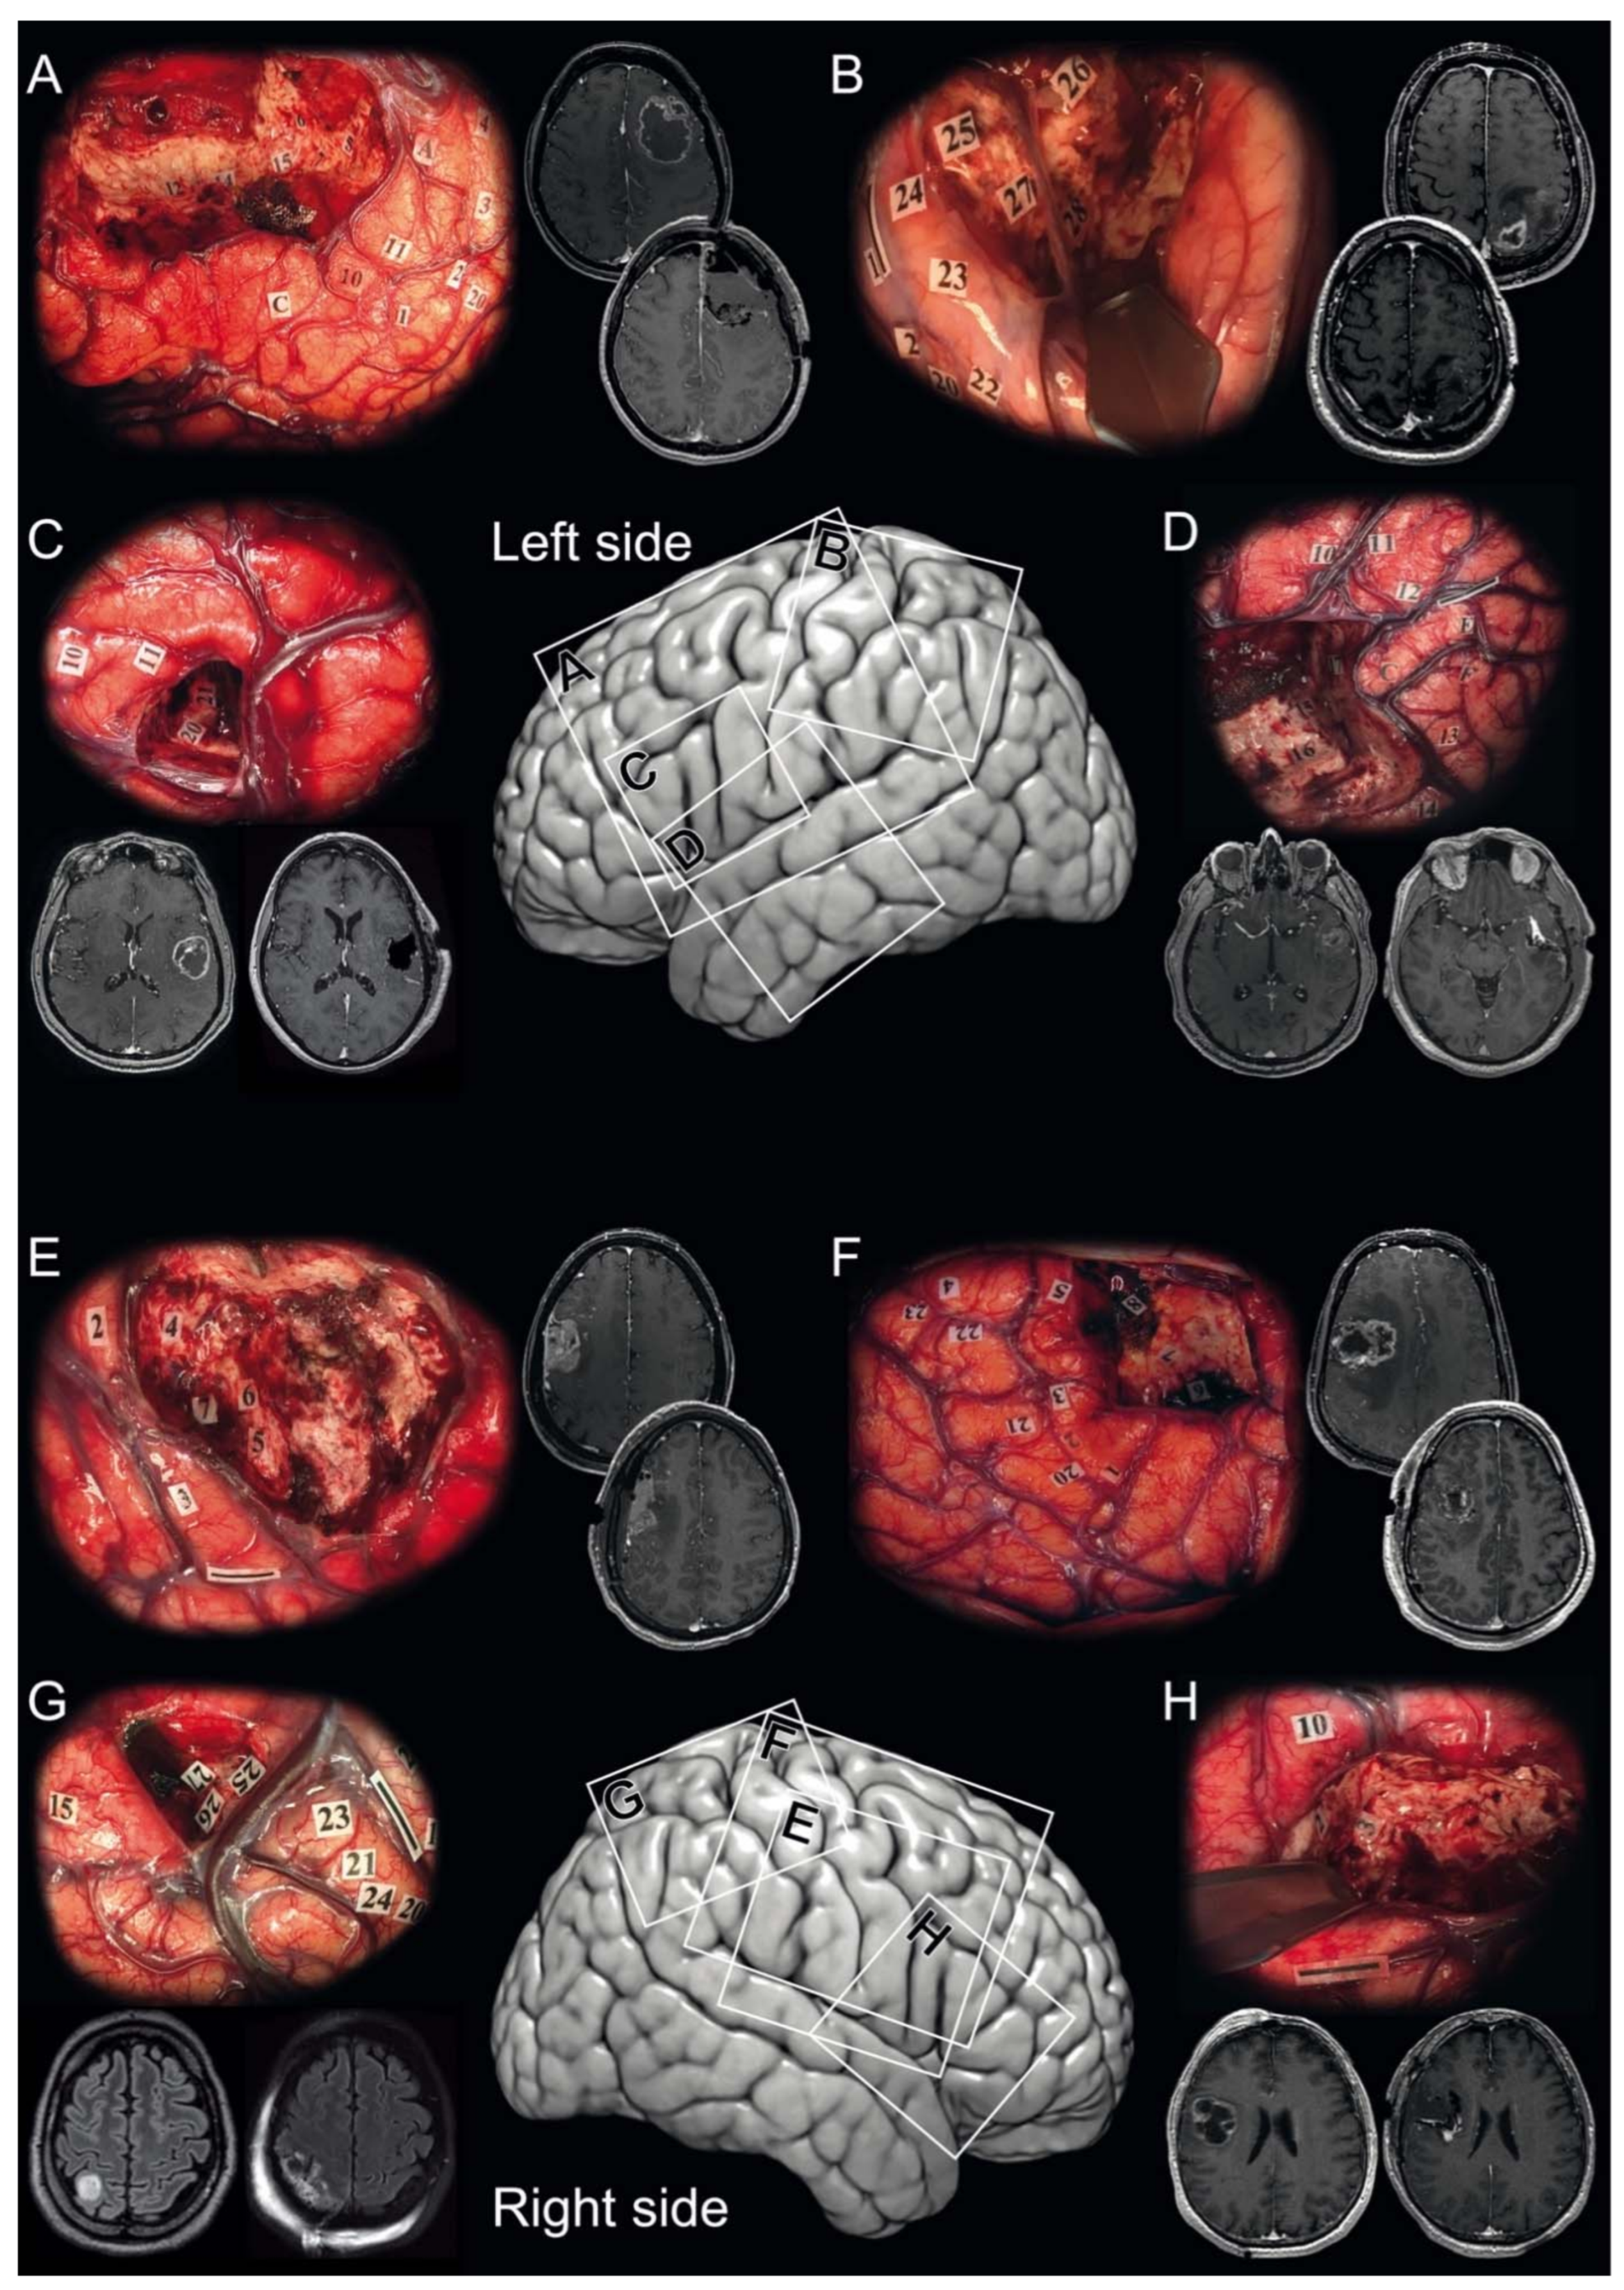

Figure 1.

Illustrative cases. Illustrative cases of isocitrate dehydrogenase (IDH)-wildtype glioblastoma awake resection using direct cortico-subcortical electric stimulations to define functional boundaries. Intraoperative photographs showing the surgical field with the functional boundaries of the resection marked intraoperatively with numbered tags in the surgical cavity and corresponding pre- and postoperative magnetic resonance post-contrast T1-weighted imaging. (A) A 46-year-old right-handed woman underwent a supratotal awake resection (36.9 cm3, no residual tumor) for a left frontal IDH-wildtype glioblastoma. (Mapping was performed at 2.0 mA. Numbered tags: involuntary movement of the mouth and tongue at 1 and 2, involuntary movement of the hand at 3 and involuntary movement of the elbow at 4 identifying the primary motor cortical pathways; paresthesias of the tongue at 20 identifying the sensory cortical pathways; anarthria at 10 and 11 identifying language cortical pathways; arrest of voluntary movements of the upper limb at 5 and 6 and arrest of voluntary movements of the upper limb and of speech at 7 identifying cortico-subcortical negative motor networks; phonemic paraphasias at 12, 14, and 15 identifying the language subcortical dorsal phonologic pathway). (B) A 45-year-old right-handed man underwent a partial awake resection (62.5 cm3, 19.7 cm3 of residual tumor) for a left parietal IDH-wildtype glioblastoma. (Mapping was performed at 5.0 mA. Numbered tags: involuntary movement of the hand occurred at 1 and 2 identifying the primary motor cortical pathways; paresthesias of the hand at 20 and 22 and paresthesias of the shoulder at 23 and 24 identifying the sensory cortical pathways; paresthesias of the lower back at 25 and 27 and paresthesias of the lower limb at 26 and 28 identifying the sensory subcortical pathways). (C) A 63-year-old right-handed woman underwent a total awake resection (14.6 cm3, no residual tumor) for a left frontal IDH-wildtype glioblastoma. (Mapping was performed at 5.0 mA. Numbered tags: anarthria occurred at 10 identifying language cortical pathways; dysarthria at 11 identifying the primary motor cortical pathways; phonemic paraphasias at 20 and 21 identifying the language subcortical dorsal phonologic pathway). (D) A 66-year-old right-handed woman underwent a total awake resection (19.6 cm3, no residual tumor) for a left temporal IDH-wildtype glioblastoma. (Mapping was performed at 5.0 mA. Numbered tags: anarthria occurred at 10, and semantic paraphasias at 13 and 14 identifying language cortical pathways; dysarthria at 11 and 12 identifying the primary motor cortical pathways; latency at 15 and 17 and semantic paraphasia at 16 identifying the language subcortical ventral semantic pathway). (E) A 44-year-old right-handed woman underwent a subtotal awake resection (18.9 cm3, 0.6 cm3 of residual tumor) for a right frontal IDH-wildtype glioblastoma. (Mapping was performed at 3.5 mA. Numbered tags: arrest of voluntary movements of the upper limb occurred at 2, 3 and 4 identifying cortico-subcortical negative motor networks; involuntary movements of the tongue at 5, 6 and 7 identifying subcortical primary motor pathways). (F) A 26-year-old left-handed man underwent a supratotal awake resection (37.9 cm3, no residual tumor) for a right frontal IDH-wildtype glioblastoma. (Mapping was performed at 2.0 mA. Numbered tags: involuntary movement of the jaw and tongue occurred at 1, 2 and 3, involuntary movement of the hand at 4, and involuntary movement of the wrist at 5 identifying the primary motor cortical pathways; paresthesias of the lips at 20 and 21, paresthesias of the thumb at 22, paresthesias of third, fourth, fifth fingers at 23 identifying the sensory cortical pathways; involuntary movements of the jaw at 7 identifying subcortical primary motor pathways; arrest of voluntary movements of the mouth at 6 and saccadic lateral deviation of the eyes at 8 identifying cortico-subcortical negative motor networks). (G) A 54-year-old left-handed man underwent a total awake resection (2.4 cm3, no residual tumor) for a right parietal IDH-wildtype glioblastoma. (Mapping was performed at 3.0 mA. Numbered tags: involuntary movement of the wrist occurred at 1 and 2 identifying the primary motor cortical pathways; paresthesias of thumb at 20, paresthesias of second and third fingers at 24, paresthesias of fourth and fifth fingers at 21 and 23 identifying the sensory cortical pathways; latency during picture naming at 15; paresthesias of the thorax at 25, paresthesias of the upper limb at 27, and paresthesias of the lower limb at 27 identifying the sensory subcortical pathways). (H) A 54-year-old right-handed woman underwent a supratotal awake resection (28.9 cm3, no residual tumor) for a right frontal IDH-wildtype glioblastoma. (Mapping was performed at 3.5 mA. Numbered tags: dysarthria occurred at 10 identifying the primary motor cortical pathways; involuntary movements of the jaw at 2 and of the lips at 3 identifying subcortical primary motor pathways).

In all cases, resection was pursued until eloquent subcortical pathways were identified, as illustrated in Figure 2.